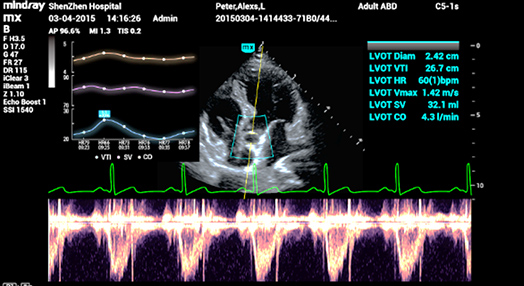

2Smart VTI

Medición automática de la VTI (integral de velocidad en función del tiempo) y CO (gasto cardíaco) para una evaluación rápida de la función cardíaca. Localización automática de la caja de color y la línea de muestra de PW en tiempo real. Gráfico de tendencias de parámetros sobre CO, SV y VTI para guiar la toma de decisiones.

2